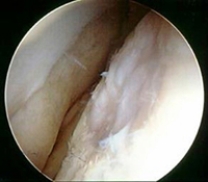

Which of the following imaging techniques illustrated in the pictures would be the most efficient to discover if there is a loose body within a joint?